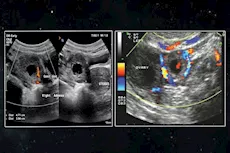

يعتبر احتباس البول من المشكلات الصحية التي تهدد الحامل، خاصةً في أواخر الثلث الأول وأوائل الثلث الثاني، من الضروري الإسراع في علاجه فور ظهور أعراضه، لتجنب تطوره لمضاعفات أكثر خطورة.

قد يكون احتباس البول ناتجًا عن الحمل خارج الرحم، وهو حالة تنغرس فيها البويضة المخصبة في مكان ما خارج الرحم، غالبًا ما يكون في تجويف البطن أو عنق الرحم.